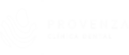

- Fase 1 – Incisión y Acceso al Seno Maxilar: El cirujano o cirujana realiza una pequeña incisión en la encía cerca de los dientes posteriores, a menudo por dentro de la boca, para evitar cicatrices visibles. Después, se accede al hueso maxilar y se perfora un pequeño agujero en la pared lateral del seno maxilar. A través de este agujero, la membrana del seno maxilar se eleva con cuidado, creando un espacio vacío.

- Fase 2 – Colocación del Injerto Óseo: Una vez que la membrana ha sido elevada, se coloca el injerto óseo (puede ser hueso autógeno del propio paciente, hueso de banco o material sintético) en el espacio creado. El injerto óseo ayuda a regenerar el hueso y a fortalecer la base para el implante.

El injerto se deja en su lugar durante varios meses para permitir que el hueso se regenere y se integre con el hueso natural, un proceso conocido como osteointegración. Después de este período de curación, se puede proceder con la colocación del implante dental.

- Fase 1 – Incisión y Acceso al Seno Maxilar: El cirujano realiza una pequeña incisión en la encía cerca de los dientes posteriores, a menudo por dentro de la boca, para evitar cicatrices visibles. Después, se accede al hueso maxilar y se perfora un pequeño agujero en la pared lateral del seno maxilar. A través de este agujero, la membrana del seno maxilar se eleva con cuidado, creando un espacio vacío.

- Fase 2 – Colocación del Injerto Óseo: Una vez que la membrana ha sido elevada, se coloca el injerto óseo (puede ser hueso autógeno del propio paciente, hueso de banco o material sintético) en el espacio creado. El injerto óseo ayuda a regenerar el hueso y a fortalecer la base para el implante.

El injerto se deja en su lugar durante varios meses para permitir que el hueso se regenere y se integre con el hueso natural, un proceso conocido como osteointegración. Después de este período de curación, se puede proceder con la colocación del implante dental.

El proceso de elevación de seno maxilar se realiza en dos fases:

- Fase 1 – Incisión y Acceso al Seno Maxilar: El cirujano realiza una pequeña incisión en la encía cerca de los dientes posteriores, a menudo por dentro de la boca, para evitar cicatrices visibles. Después, se accede al hueso maxilar y se perfora un pequeño agujero en la pared lateral del seno maxilar. A través de este agujero, la membrana del seno maxilar se eleva con cuidado, creando un espacio vacío.

- Fase 2 – Colocación del Injerto Óseo: Una vez que la membrana ha sido elevada, se coloca el injerto óseo (puede ser hueso autógeno del propio paciente, hueso de banco o material sintético) en el espacio creado. El injerto óseo ayuda a regenerar el hueso y a fortalecer la base para el implante.

El injerto se deja en su lugar durante varios meses para permitir que el hueso se regenere y se integre con el hueso natural, un proceso conocido como osteointegración. Después de este período de curación, se puede proceder con la colocación del implante dental.